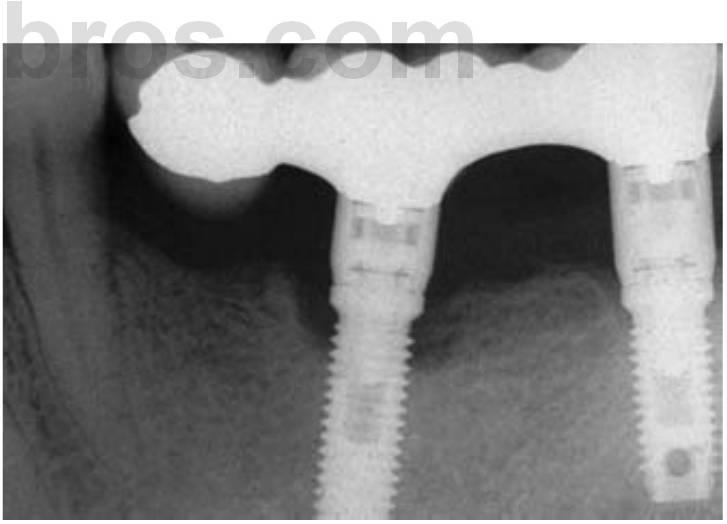

En algunas ocasiones, un implante puede fracasar poco tiempo después de haberse empezado a «integrar» en el hueso. Antes del fracaso, el implante parece tener una fijación rígida, y todos los indicadores clínicos están dentro de la normalidad. En cualquier caso, una vez que el implante está cargado, se vuelve móvil en el plazo de entre 6 y 18 meses (fig. 4-1). Esto ha sido denominado fracaso temprano por carga por Misch y Jividen. La causa de este fracaso temprano por carga suele ser un estrés excesivo para la interfase hueso-implante. Isidor permitió la integración de ocho implantes en mandíbulas de monos. Las coronas se sujetaban a los implantes cicatrizados con un exceso de contactos oclusales prematuros. Sobre un período de 20 meses, seis de los ocho implantes fracasaron (fig. 4-4). En estos mismos animales, ocho implantes integrados sin cargas oclusales llevaban unas anillas colocadas en el margen gingival para aumentar la retención de placa. Ninguno de estos implantes fracasó a lo largo de los siguientes 20 meses. Los autores concluyeron que en este modelo de animal, el estrés oclusal biomecánico era un mayor factor de riesgo para el fracaso temprano por carga que el componente biológico de la placa bacteriana.